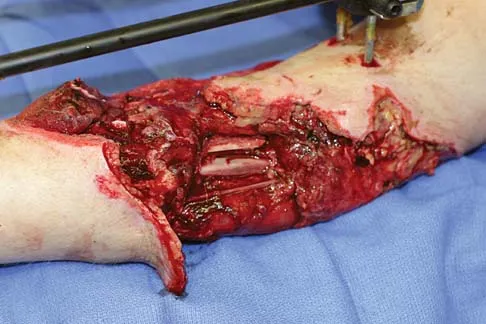

Question 31

A 24-year-old man has right forearm pain after sliding head first into home plate. Examination reveals that the arm is swollen, but there are no neurovascular deficits or skin lacerations. Radiographs reveal a both-bone forearm fracture. The ulna has an oblique fracture with a 30% butterfly fragment, and the radius is comminuted over 75% of its circumference. In addition to reduction and plate fixation of both bones, management should consist of